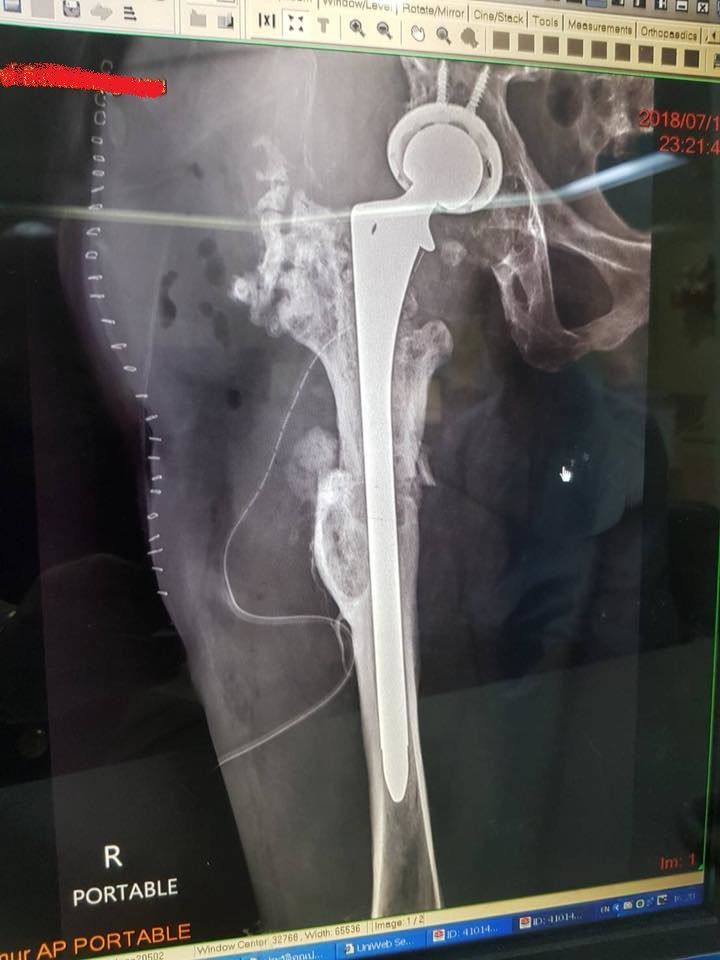

มีรูป X-ray มาให้ดูด้วย จากภาพกระดูกกำลังอยู่ในช่วงสมานตัวกันอยู่ตามที่หมอบอกน่ะนะ เหล็กที่ใส่คราวนี้ยาวกว่าเดิมด้วยนะเนี่ย หมอบอกว่าฝังให้ลึกกว่าเดิมเพื่อความแน่น ส่วนด้านขวาคือรอยแม็คเย็บแผล